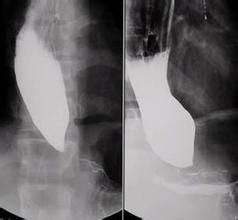

賁門失遲緩症二、食管擴張療法:套用氣囊或探條擴張,使食管與胃的連線處得鬆弛。在透視下經口插入以探條為前導的氣囊,使探條進入胃口,而氣囊固定於食管與胃的連線處,注氣或注液,出現胸痛時停止注氣或注液,留置5~10分鐘後拔出。一次治療後經5年隨訪,有效率達60%~80%。有效標準為因下困難消失,可以恢復正常飲食。